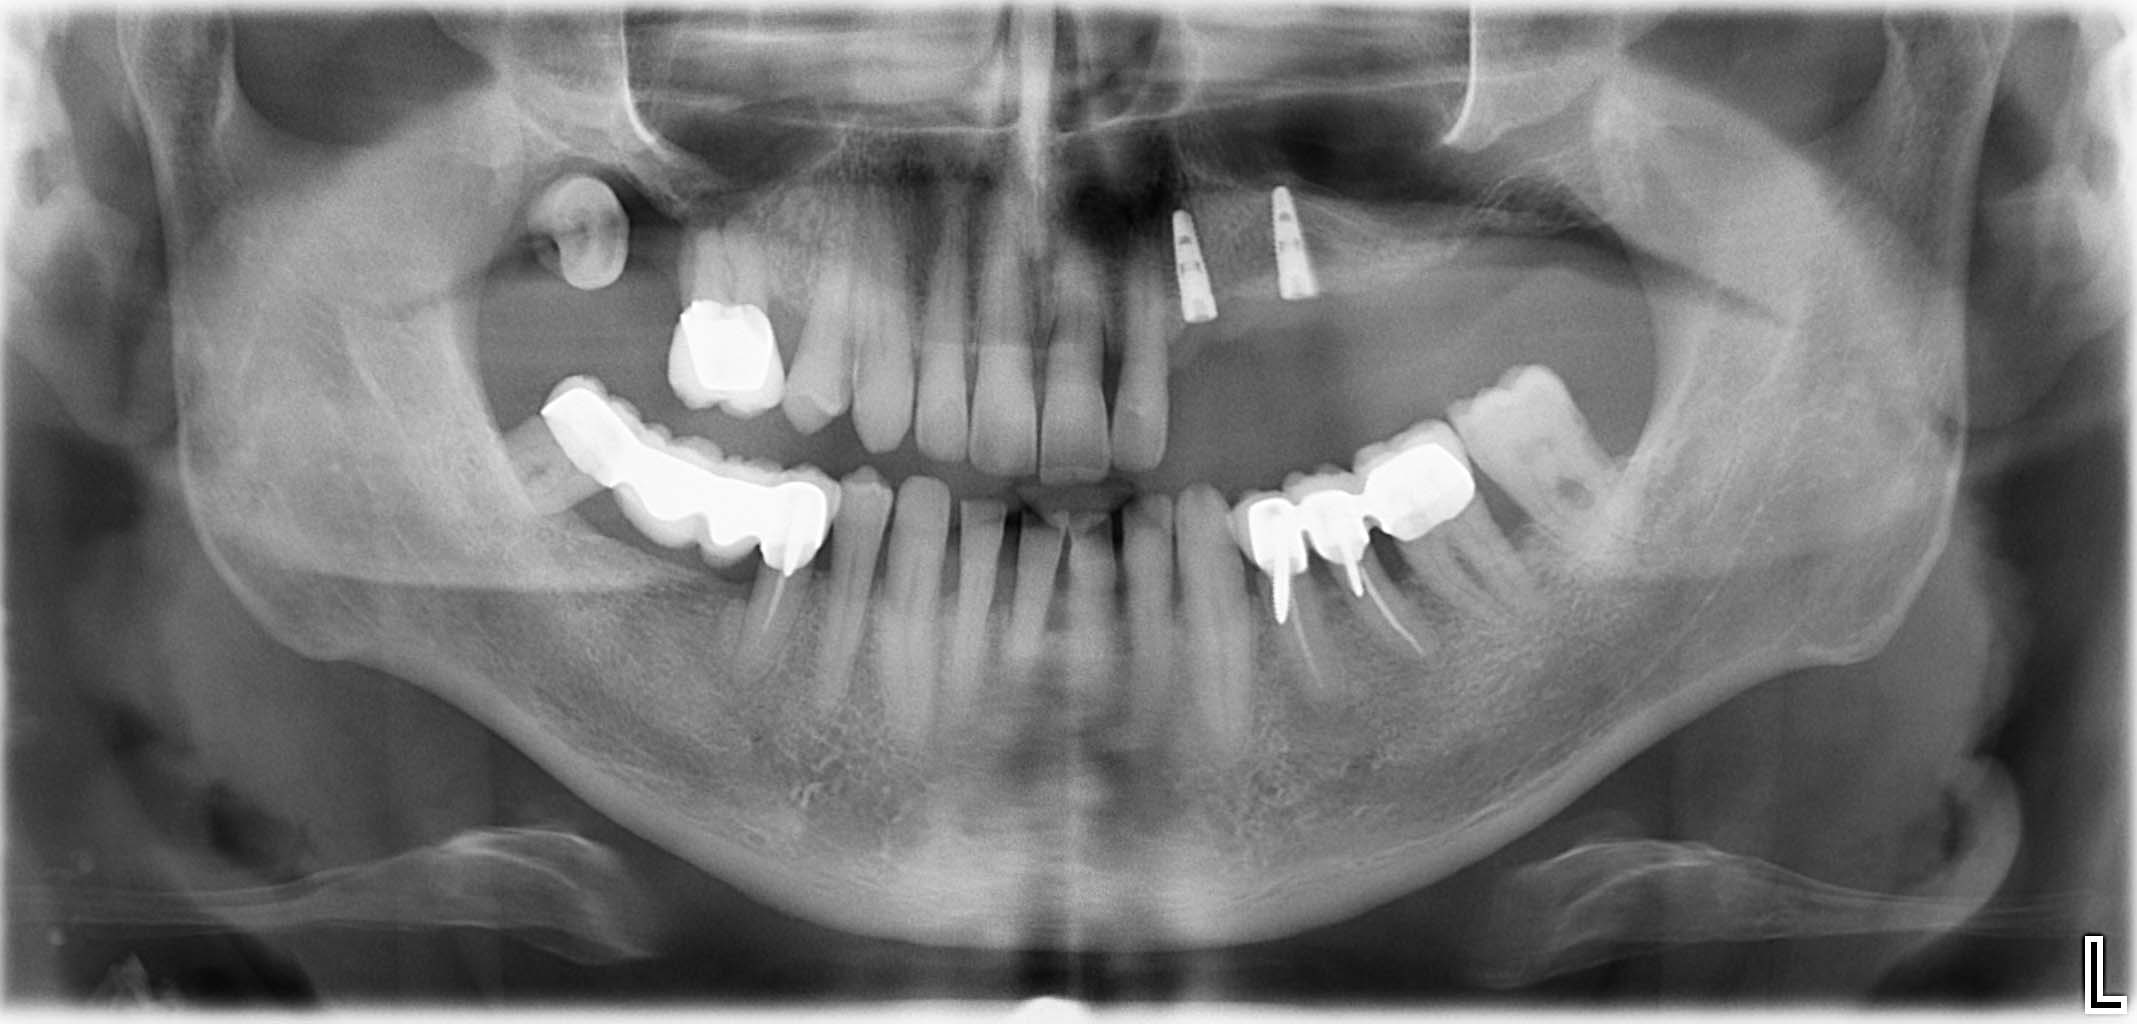

Erfolgreich implantierte Patientenfälle (klinische Fotos)